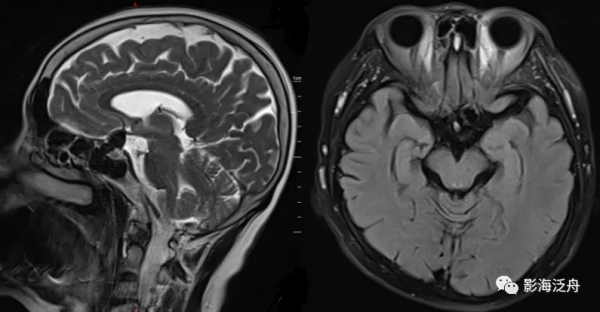

病例二:患者女,78歲,頭暈1周,無頭痛、惡性嘔吐等症狀,既往有胃CA手術史和糖尿病、高血壓等病史。

病例二:左側前交通動脈動脈瘤。動脈瘤瘤體顯示清晰,呈流空改變,內見斑片狀T2WI稍高訊號影,可能是湍流造成的。如果腦子裡完全沒有去觀察顱內血管的意識,那就很容易漏診。